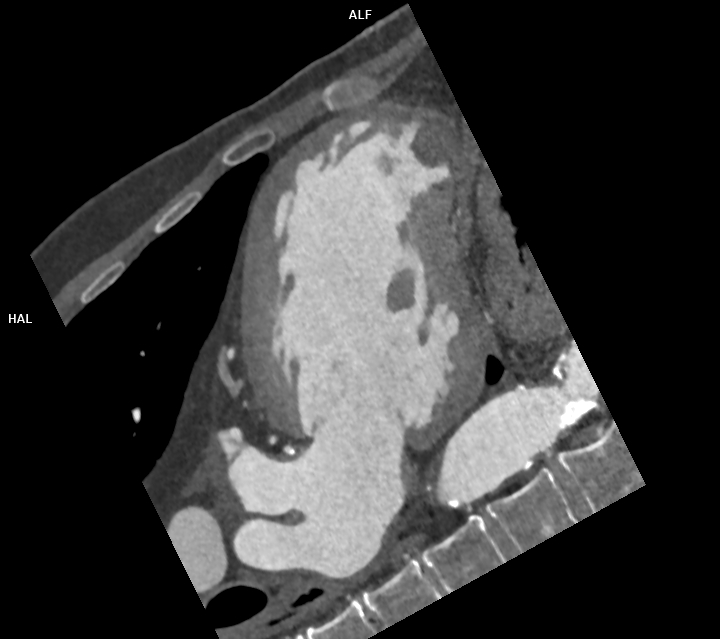

Figura 4: reconstrucție mutiplanară 2 camere din achiziție angioCT coronariană cu sincronizare ECG

Discuţie caz nr 120: Achiziția angioCT coronariană cu sincronizare ECG evidențiază ocluzie a arterei descendente anterioare în segmentul mediu cu hipokinezie severă / diskinezie a miocardului deservit și formarea unui anevrism antero-septal și apical ventricular stâng ce este locuit de un tromb.